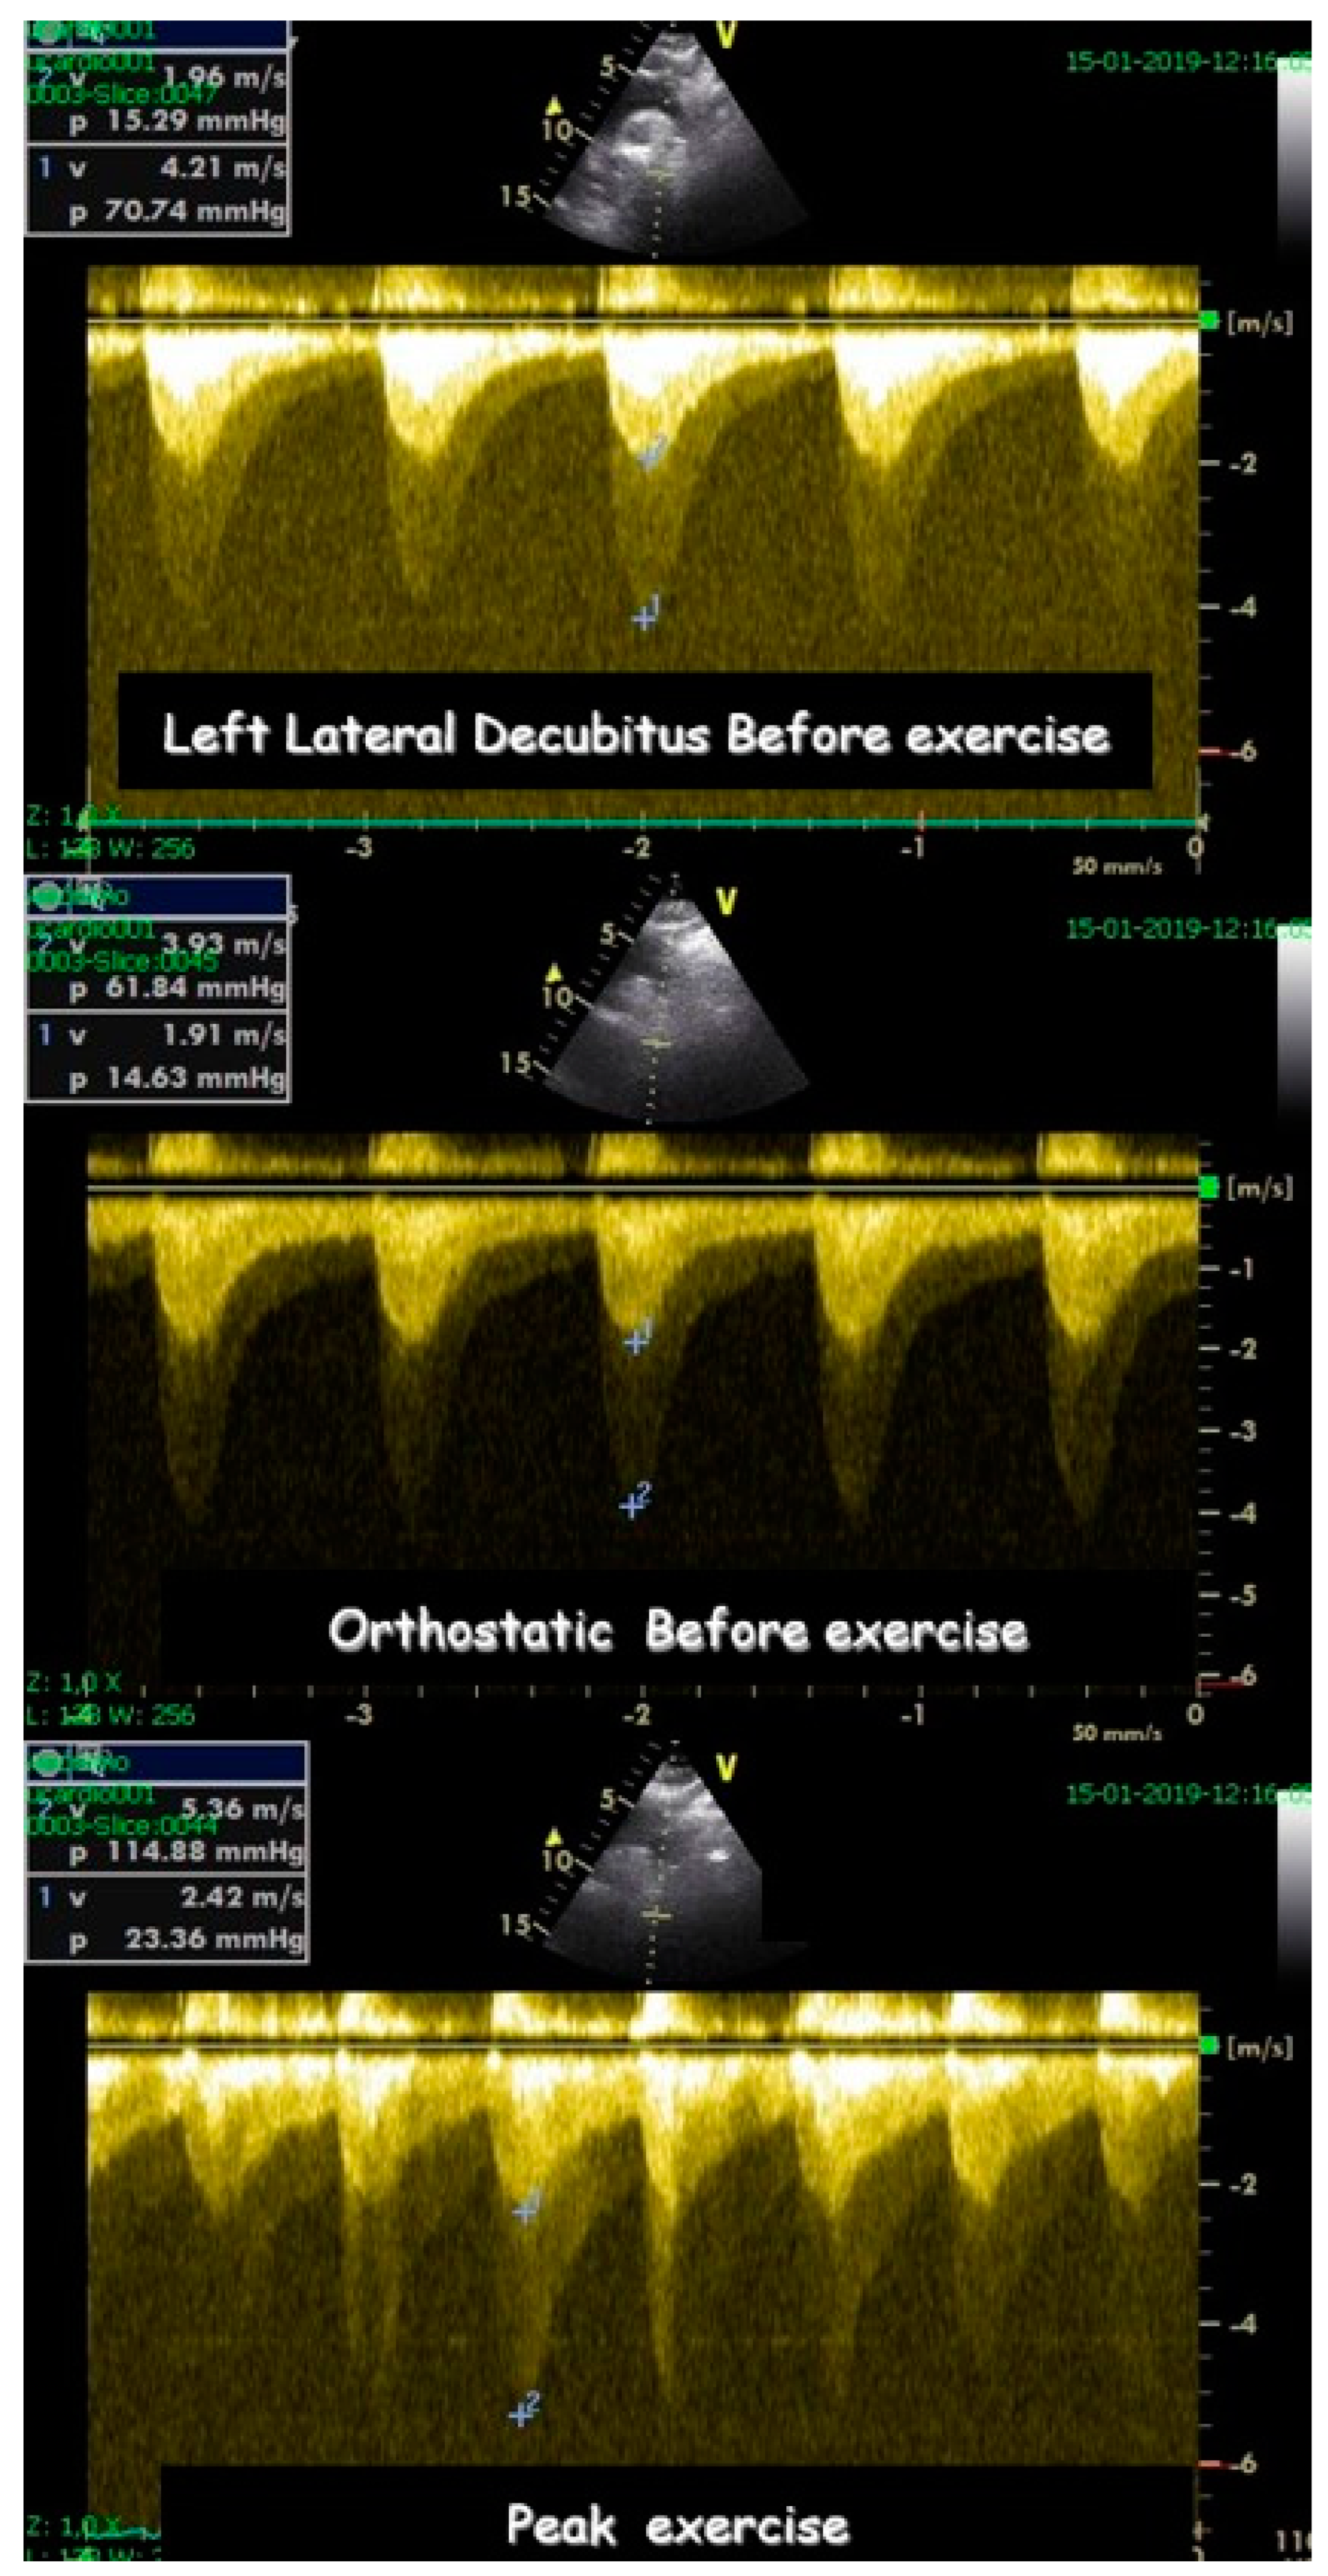

- Cotrim, C.; Palinkas, E.D.; Cotrim, N. The Importance of Left Ventricular Outflow Tract and Mid-Ventricular Gradients in Stress Echocardiography: A Narrative Review. J. Clin. Med. 2023, 12, 5292. [Google Scholar] [CrossRef] [PubMed]

- Cabrera-Bueno, F.; García-Pinilla, J.M.; Gómez-Doblas, J.J.; Montiel-Trujillo, A.; Rodríguez-Bailón, I.; de Teresa-Galván, E. Beta-blocker therapy for dynamic left ventricular outflow tract obstruction induced by exercise. Int. J. Cardiol. 2007, 117, 222–226. [Google Scholar] [CrossRef] [PubMed]

- Cotrim, C.; Lopes, L.R.; Almeida, A.R.; Miranda, R.; Ana, A.G.; Cotrim, H.; Andrade, J.P.; Picano, E.; Carrageta, M. Efficacy of beta-blocker therapy in symptomatic athletes with exercise-induced intra-ventricular gradients. Cardiovasc. Ultrasound. 2010, 8, 38. [Google Scholar] [CrossRef] [PubMed]

- Cabrera Bueno, F.; Rodríguez Bailón, I.; López Salguero, R.; Doblas, J.J.G.; Cabeza, A.P.; Hernández, J.P.; Franco, A.D.; Hidalgo, L.M.; de Teresa Galván, E. Obstrucción dinámica intraventricular izquierda inducida por esfuerzo [Dynamic left ventricular outflow tract obstruction induced by exercise]. Rev. Esp. Cardiol. 2004, 57, 1179–1187. [Google Scholar] [CrossRef] [PubMed]

- Zywica, K.; Jenni, R.; Pellikka, P.A.; Faeh-Gunz, A.; Seifert, B.; Attenhofer Jost, C.H. Dynamic left ventricular outflow tract obstruction evoked by exercise echocardiography: Prevalence and predictive factors in a prospective study. Eur. J. Echocardiogr. 2008, 9, 665–671. [Google Scholar] [CrossRef]

- Saeed, S.; Vegsundvåg, J. Usefulness of Stress Echocardiography in Assessment of Dynamic Left Ventricular Obstructions: Case Series and Review of the Literature. Cardiology 2021, 146, 441–450. [Google Scholar] [CrossRef]

- Alhaj, E.K.; Kim, B.; Cantales, D.; Uretsky, S.; Chaudhry, F.A.; Sherrid, M.V. Symptomatic exercise-induced left ventricular outflow tract obstruction without left ventricular hypertrophy. J. Am. Soc. Echocardiogr. 2013, 26, 556–565. [Google Scholar] [CrossRef] [PubMed]